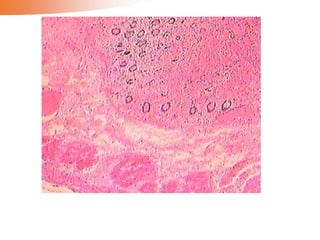

•Myocardial infarct

The myocardial

cells shows

coagulative

necrosis with the

outline of the

myocardium. In

the margin of the

infarct there are

numerous

inflammatory

exudation and

connective tissue.

•Myocardial infarct The myocardial cellsshows coagulative necrosis with the outline of the myocardium. In the margin of the infarct there are numerous inflammatory exudation and connective tissue.